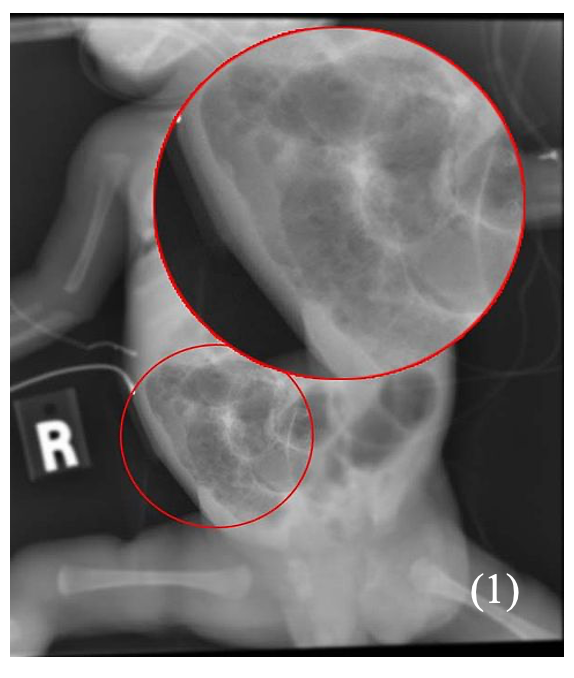

Abdominal x-ray –> air in dilated bowel, pneumatosis (air in bowel wall), rigler sign (if bowel perforation)

– Chest X-ray shows a diffuse granular or ‘ground glass appearance’ with air bronchograms

Chest X-ray shows hyperinflation, atelectasis and cystic changes